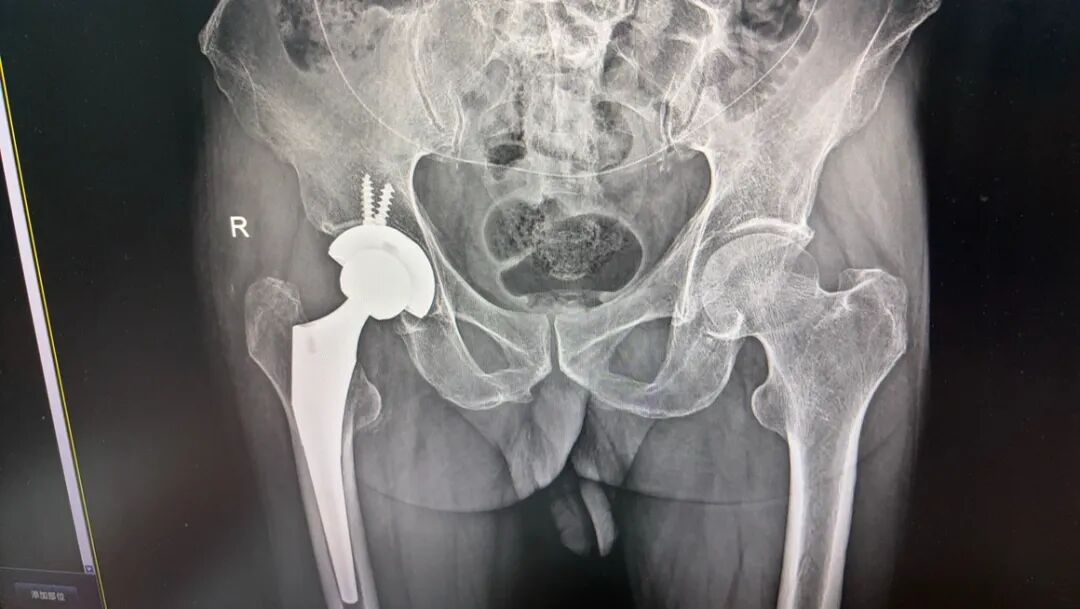

(病例拍摄已经过患者及家属知情同意)

复位成功后应立即行X线摄片和CT 扫描,评估复位情况和是否合并股骨头、髋臼的 骨折,如果髋臼和股骨头的同心结构未能恢复,髋关节仍处于半脱位,提示股骨头或髋臼骨折,需进一步手术治疗,重建髋关节的稳定性。